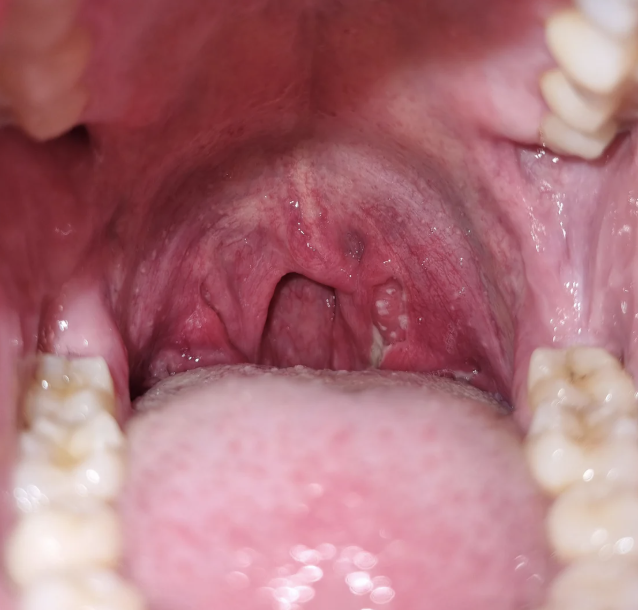

Tonsillitis is the inflammation of the tonsils. Tonsils are two oval-shaped pads of lymphoid tissue located at the back of the throat and form an important part of the immune system. They act as filters by trapping bacteria and viruses that could otherwise enter the airways and cause infection. Tonsils also help the body by producing antibodies to fight infections.

Common symptoms include swollen tonsils, painful or difficult swallowing, red throat, high-grade fever, and white or yellow patches on the tonsils. Enlarged neck glands, sore throat, muffled or altered voice, headache, low appetite, and ear pain are also frequent. Some individuals experience breathing difficulty through the mouth, persistent bad breath, fatigue, nausea, or voice changes. In some cases, tonsilloliths or tonsillitis develop when debris becomes trapped. Occasionally, tonsils may enlarge enough to touch each other, a condition described as “kissing tonsils,” which may further obstruct airflow.

Diagnosis usually begins with a clinical examination of the throat, where enlarged, red, or swollen tonsils may be observed, along with inflamed lymph nodes. The doctor may also assess associated symptoms such as fever, voice changes, difficulty swallowing, or breathing discomfort.